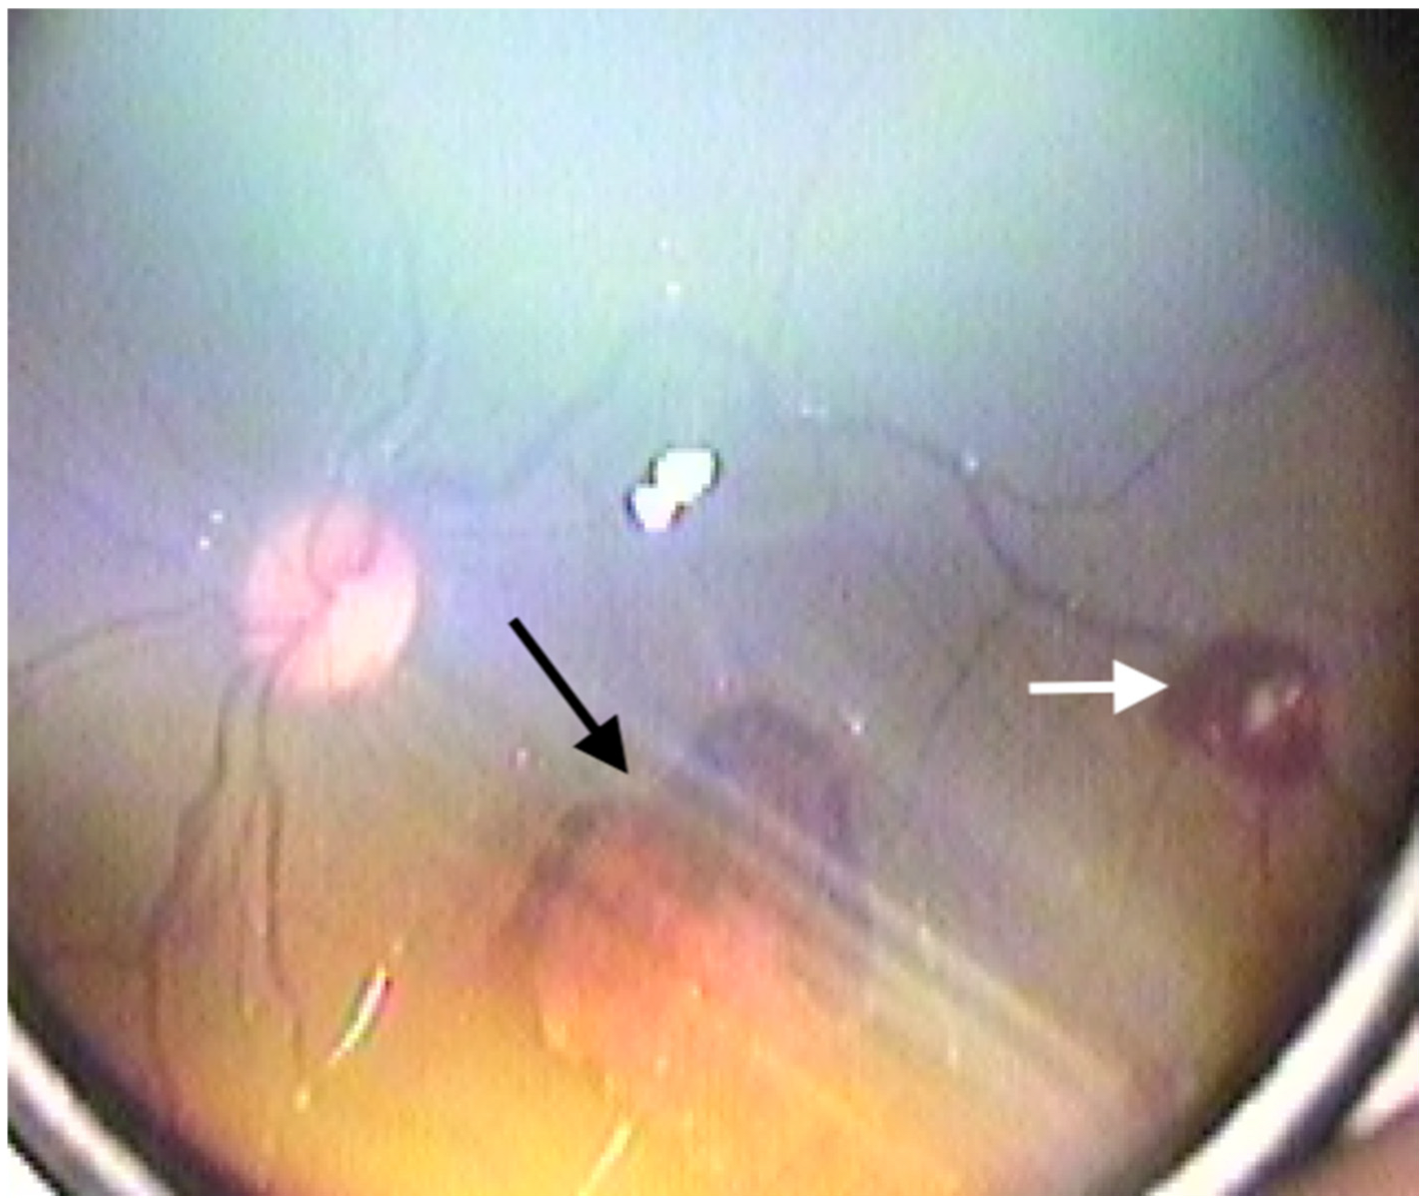

Retinal hemorrhages were identified in 178 eyes (42.3%), while RS were observed in 180 eyes (42.8%). The prevalence of both RH and RS was significantly higher in neonates with Stage 2 and Stage 3 HIE (p < 0.001). Examples of retinal hemorrhages and Roth spots are presented in Figure 1, Figure 2 and Figure 3. The mean resolution time for RH and RS was 20.21 ± 6.19 days and 13.3 ± 2.2 days, respectively. Notably, the resolution time for RH and RS was significantly prolonged in the Stage 3 HIE group compared to the other groups (p < 0.001). Moreover, an increasing HIE stage was associated with more severe RH, as classified by the Egge classification system. Detailed data regarding RH are presented in Table 2. Importantly, all instances of RH and RS were bilateral.

Figure 3. Grade 3 retinal hemorrhage (black arrow) and Roth spot (white arrow).

Retinal hemorrhages were classified into three grades according to the classification proposed by Egge et al. [16]. Grade 1 RH were defined as small hemorrhages within a limited area, characterized by fine linear bleeding confined to the peripapillary region. Grade 2 RH included a slightly larger extent of hemorrhage, with patchy, flame-shaped bleeding extending over an area not exceeding the diameter of the optic disc. Grade 3 RH were characterized by hemorrhages exceeding the optic disc diameter, accompanied by flame-shaped bleeding along the retinal vasculature and macular involvement. As Roth spots are not incorporated into this classification system, they were documented separately when observed.

Roth spots are superficial retinal hemorrhages located in the nerve fiber layer, characterized by a central white dot. They result from capillary rupture, leading to hemorrhage with a central fibrin-platelet cluster [8]. The underlying mechanisms of capillary damage include hypoxia, trauma, and inflammation. While RS have historically been associated with infective endocarditis [9], they have also been identified in various other systemic and ophthalmological conditions, including leukemia and shaken baby syndrome [10,11]. In our study, RS were observed in 42.8% of neonates with HIE. Moreover, logistic regression analysis identified higher HIE stages as independent risk factors for RS development. The increasing prevalence of RS with worsening ischemia underscores the impact of ischemia and hypoxia on the retinal vascular structure in HIE. The presence of RS in neonates with HIE highlights the importance of comprehensive retinal examinations in neonates with systemic ischemic conditions, as these findings may provide valuable prognostic information.